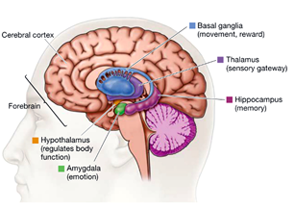

Amygdala: What It Is and What It Controls

Know Your Brain: Amygdala

Amygdala Function and Location

Amygdala's Location and Function

The limbic system - Queensland Brain Institute - University of

Amygdala: Anatomy, Location, and Function

The Limbic System